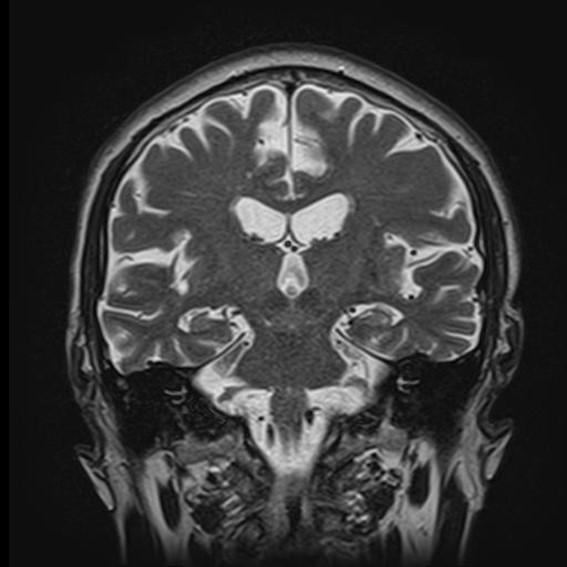

運用高科技尖端影像設備,提供貴賓精準的檢查、判讀、即時醫療、後續追蹤、健康管理或醫學中心轉介服務;從健檢診斷到後端治療,一條龍式服務。永越自成立以來,已服務超過16萬人次,每年通報件數超過千件,揪出包括:甲狀腺癌、肝腫瘤、肺癌、乳癌、子宮頸癌等重大異常的健康警訊,把握住早發現早治療的黃金關鍵。